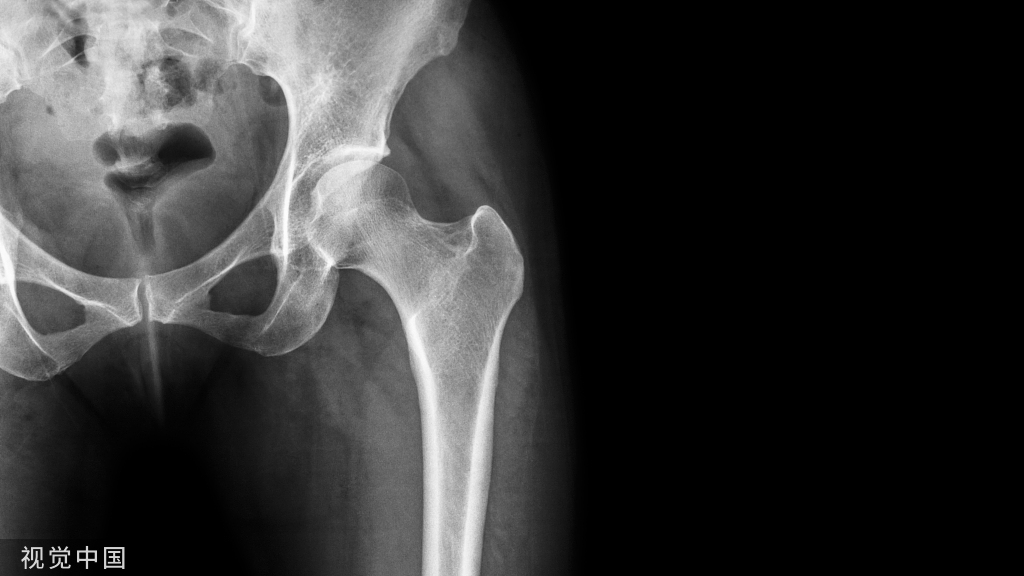

髋关节的X线解剖及应用技巧,最全总结!

目前,一张标准的X片图像仍然能为我们的临床诊断与决策提供重要的依据。为了全面评估髋部疼痛患者的病情,X线片图像仍然是有效手段。